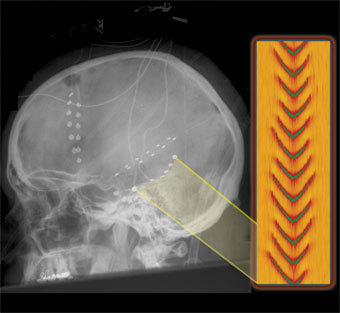

Энцефалограмма эпилептического припадка, изображение с сайта berkeley.edu

Пики на теоретической и экспериментальной энцефалограммах обладают одинаковой формой и близкими амплитудами, что подтверждает "работоспособность" метода. Расчеты, описывающие пока отдельные аспекты патофизиологии мозга, смогут в перспективе прояснить многие детали мыслительной деятельности, считает доктор Хейди Кирш (Heidi Kirsch), возглавляющий группу исследователей.